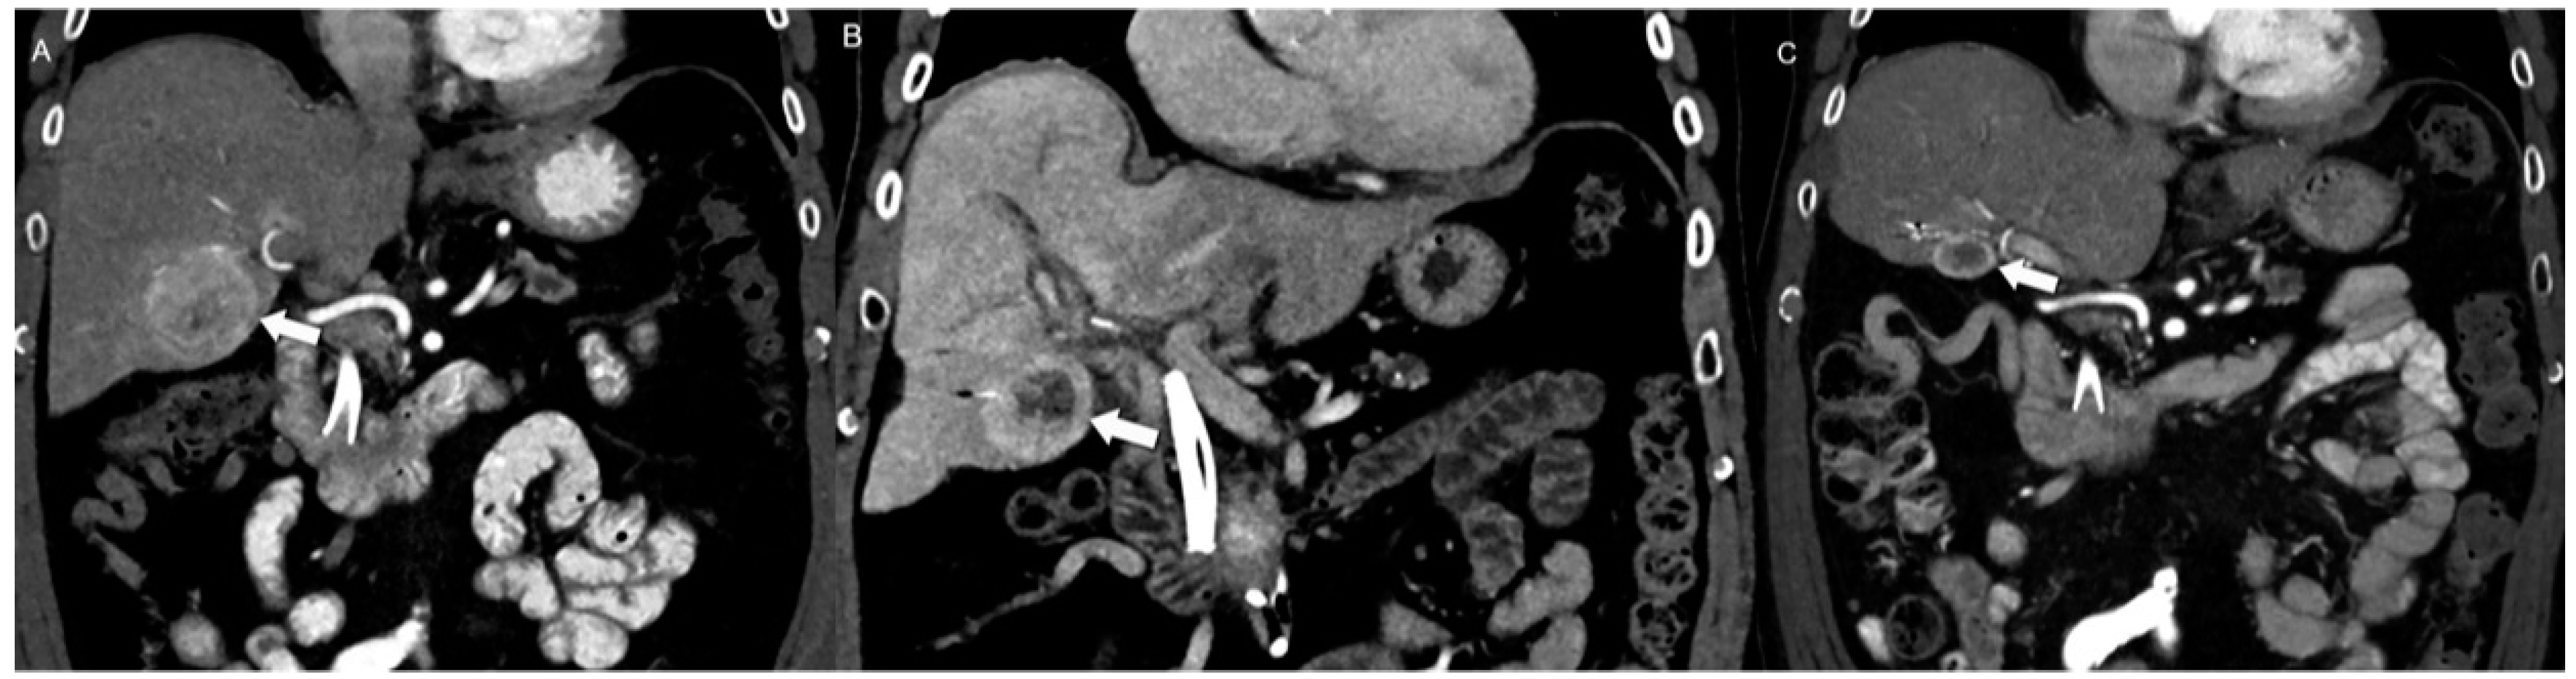

4.1. Morphologic Imaging of NENs